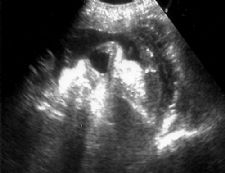

Normal appearing cervix. Closed and long.

Length cervical canal

10-50 mm in 2nd and 3rd trimesters

50th% is 3.5 cm

10th% is 2.5 cm

90th% is 4.5 cm

- Cervical length < 2.5 cm at 22-24 weeks 6x increase in PTB before 35 weeks.

Shortening of cervix with mild funneling.- Often see shortening with bleeding/contractions/multiple gestation with delivery < 32 weeks

- Cervical length 1.8-2.0 cm best positive predictive value.

Marked funneling of cervix with shortening.- Cervical length 3.0 cm excludes preterm labor